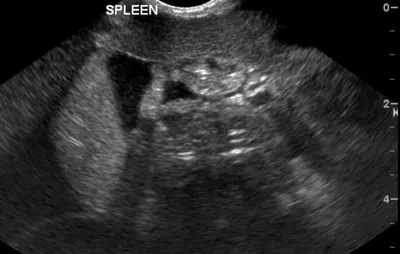

Advantages_Diagnosis & Monitoring_The primary advantage of using FAST and TFAST examinations in patients after a traumatic event is the ability to diagnose and monitor abdominal or thoracic effusions or a pneumothorax with relative ease and in a very short time (Figures 1 and 2).

Figure 1: Free abdominal fluid around the spleen visualized with an abdominal FAST examination

An ultrasound image showing the spleen of a veterinary patient, with the organ appearing as a textured structure in shades of gray. The image includes labeled anatomical details, indicating the spleen's position within the abdominal cavity.